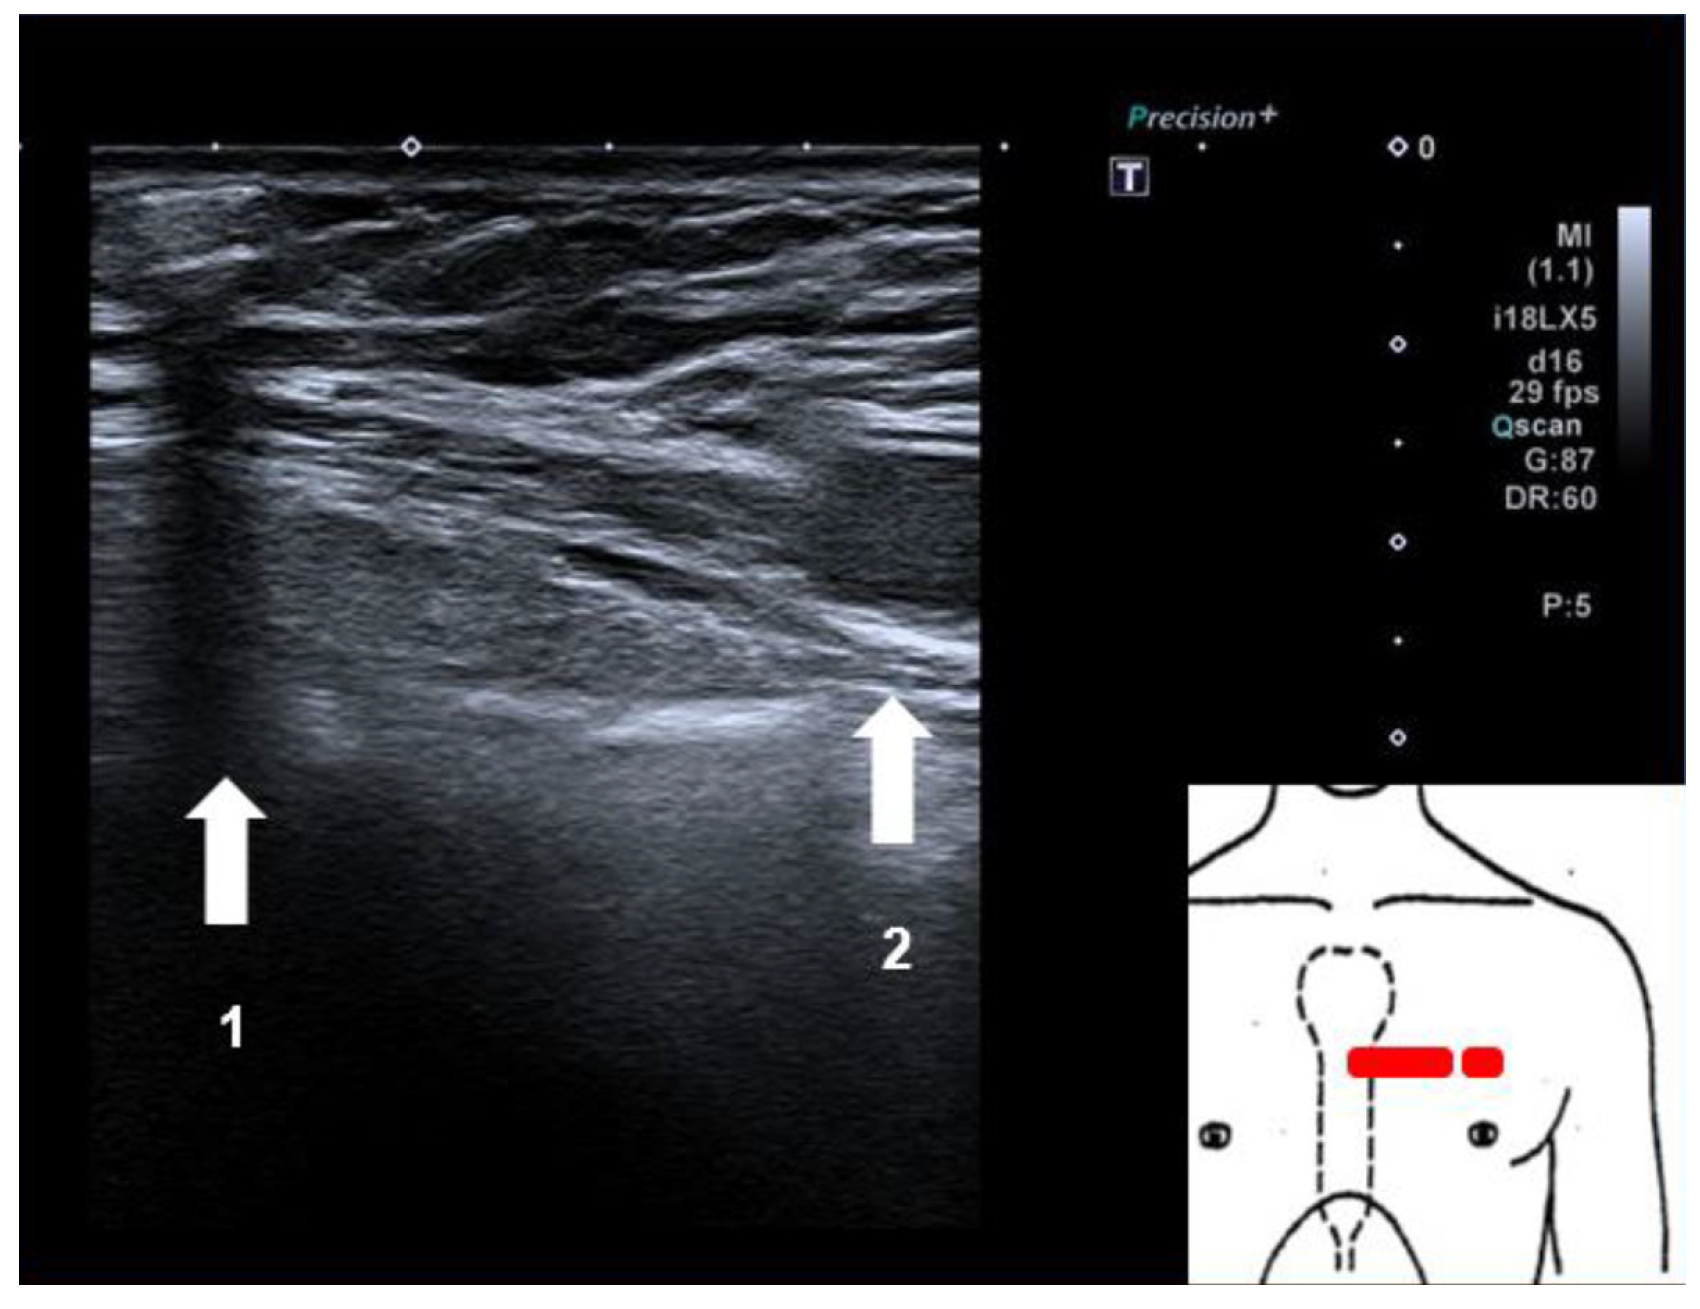

Figure 2. Sonographic check of the device position in relation to the silicone breast implant: 1. Subcutaneous ILR with posterior ultrasound shadow. 2. Medial boarder of left silicone breast implant.

After defining a sterile field and disinfecting the local area, ultrasound-guided subcutaneous local anaesthesia was performed, in the direction of the planned implantation orientation of the device (parallel to the left sternal boarder, caudally, starting in the fourth intercostal space). After this, we inserted the device with ultrasound guidance in the direction in which the local anaesthetic was administered, following the manufacturers recommendations on how to implant their device. A sonographic check showed that there was sufficient subcutaneous tissue between the loop recorder and the medial boarder of the left silicone implant (Figure 2). The initial device interrogation revealed a sensing level of more than 0.3 mV (lying and sitting positions) with a clearly visible P-wave and good discrimination of the QRS-complex (Figure 3). The patient was discharged after a few minutes of clinical observation with normal vital signs and no specific complaints.